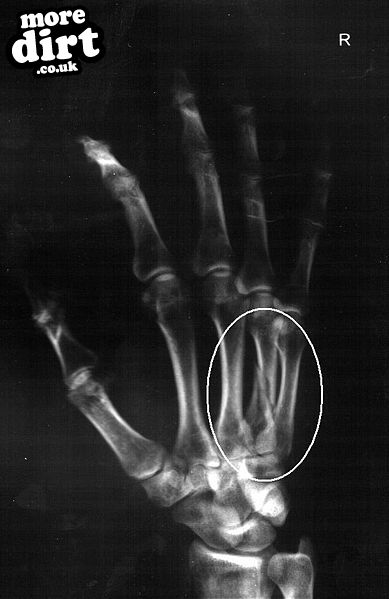

Thats the bone I broke at the weekend

THAT IS A PUNCHING INJURY. HAD 3 SO FAR TRIED LYING TO THE DOC 3 TIMES, AND 3 TIMES HES TOLD ME AM FULL OF SH1T. LOL